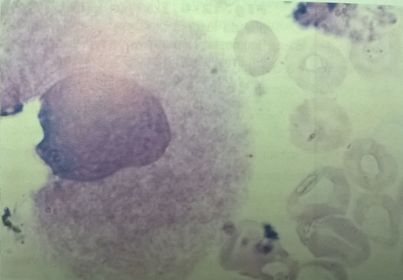

Megacarioblasto

Figura 26 Megacarioblasto por microscopía óptica

(Carr & Rodak, 2010).